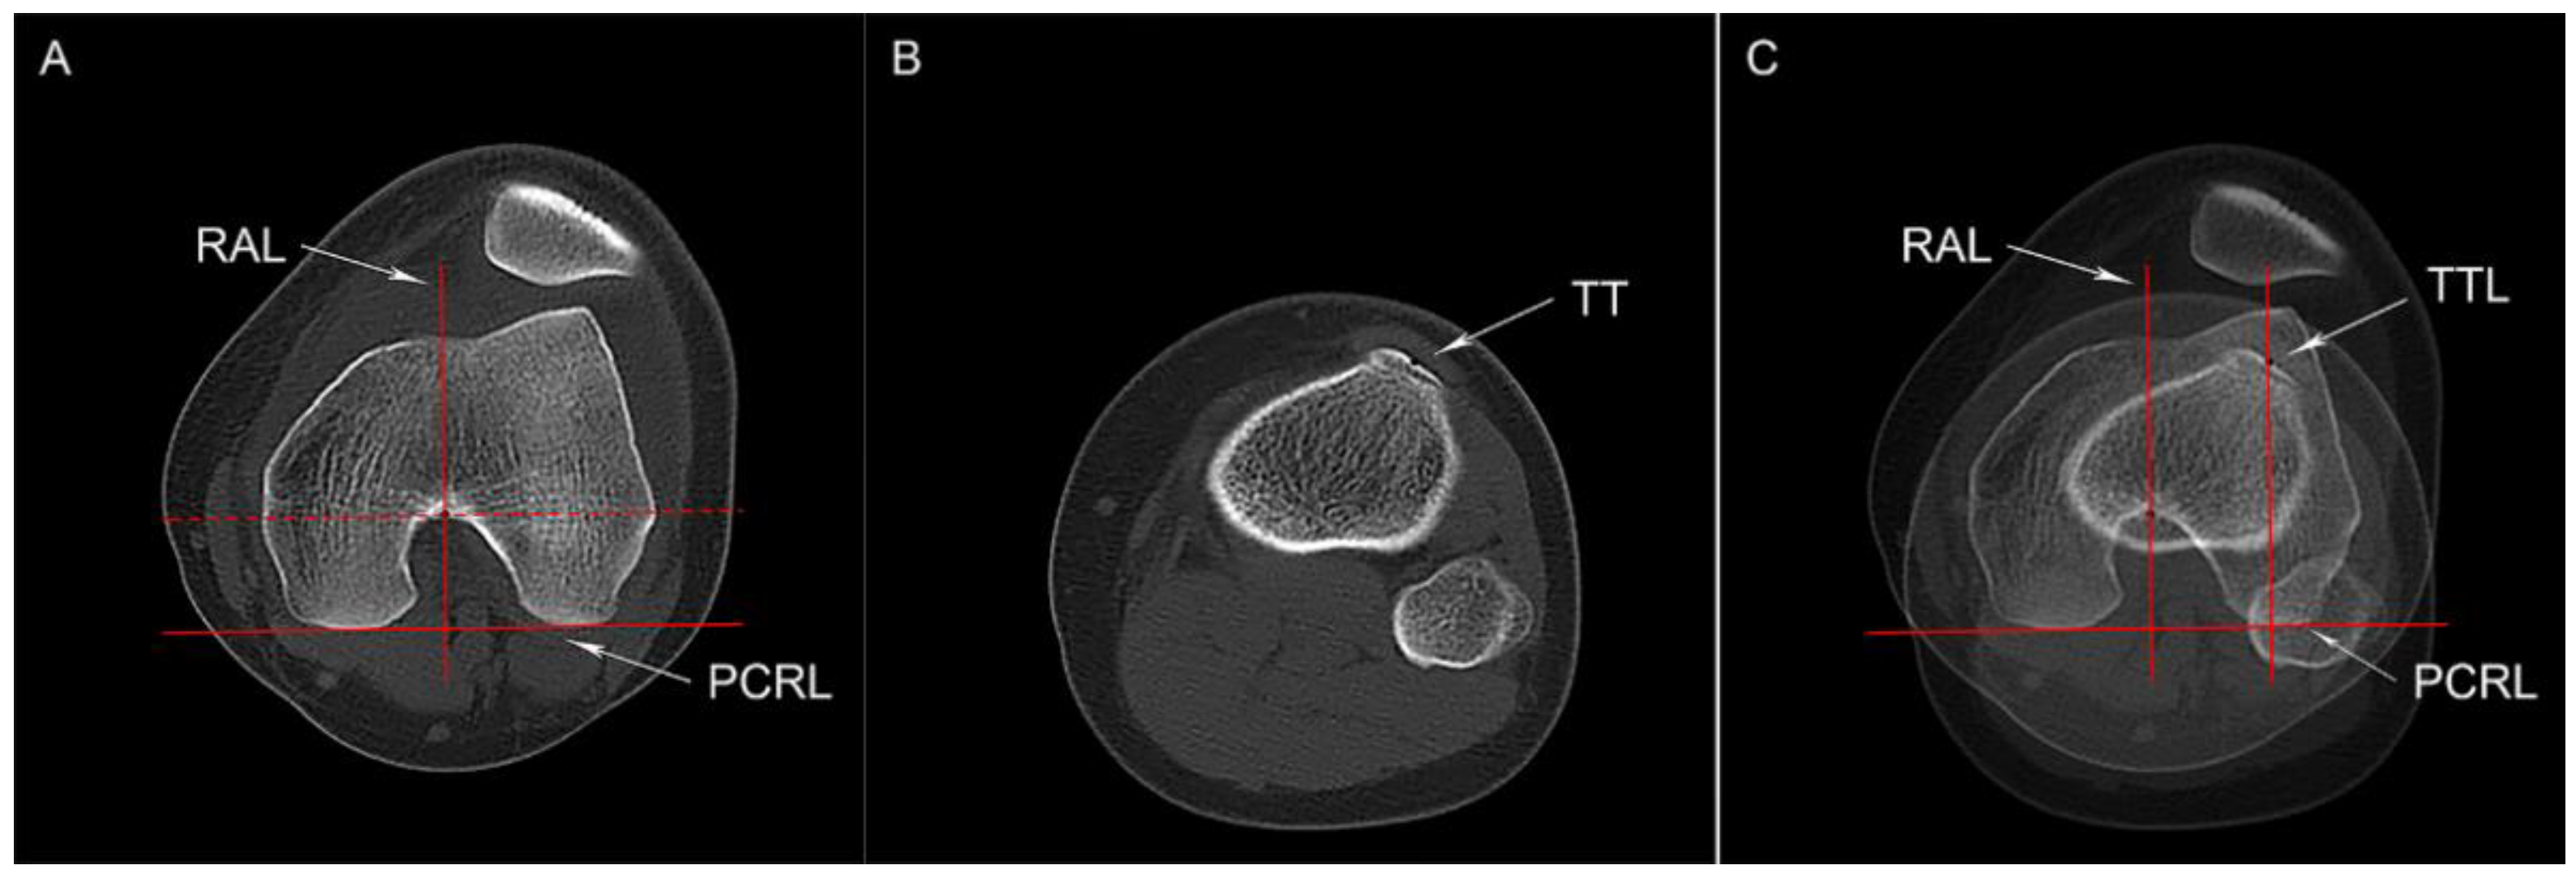

2.3.2. Tibial Tubercle Lateralization